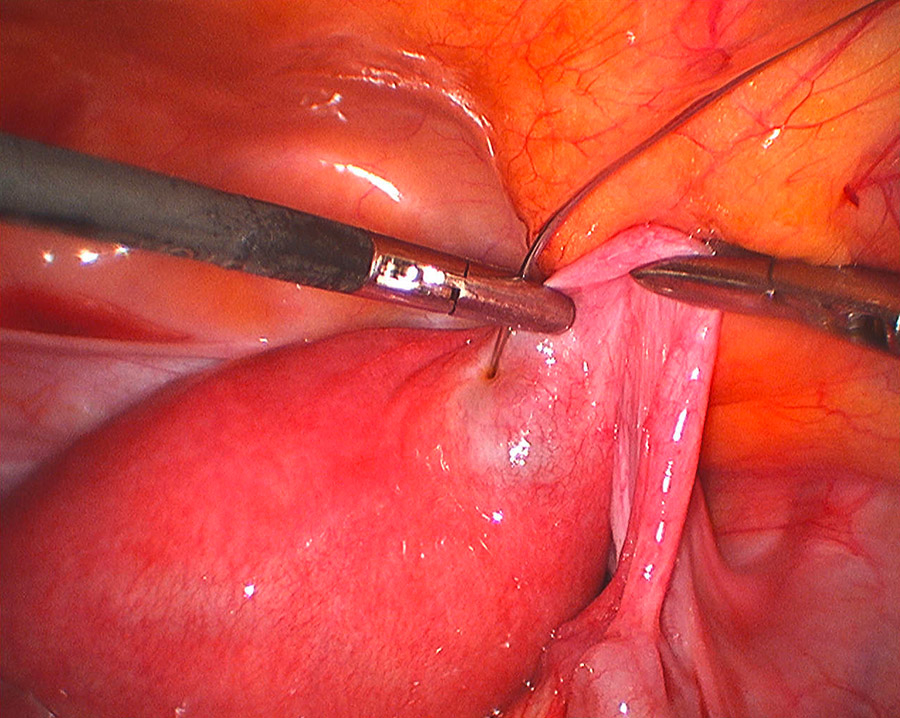

Figure 2

Laparoscopic intracornual MTX injection.

Nine patients were treated with MTX whereas two had a cornual resection during a diagnostic laparoscopy, converted to laparotomy in one case. Three out of nine patients were treated with intramuscular MTX (IM-MTX) and in the remaining six MTX was injected directly into the cornual region (IC-MTX): in four cases during a laparoscopy (fig. 2) and in two cases during a transvaginal ultrasound procedure.